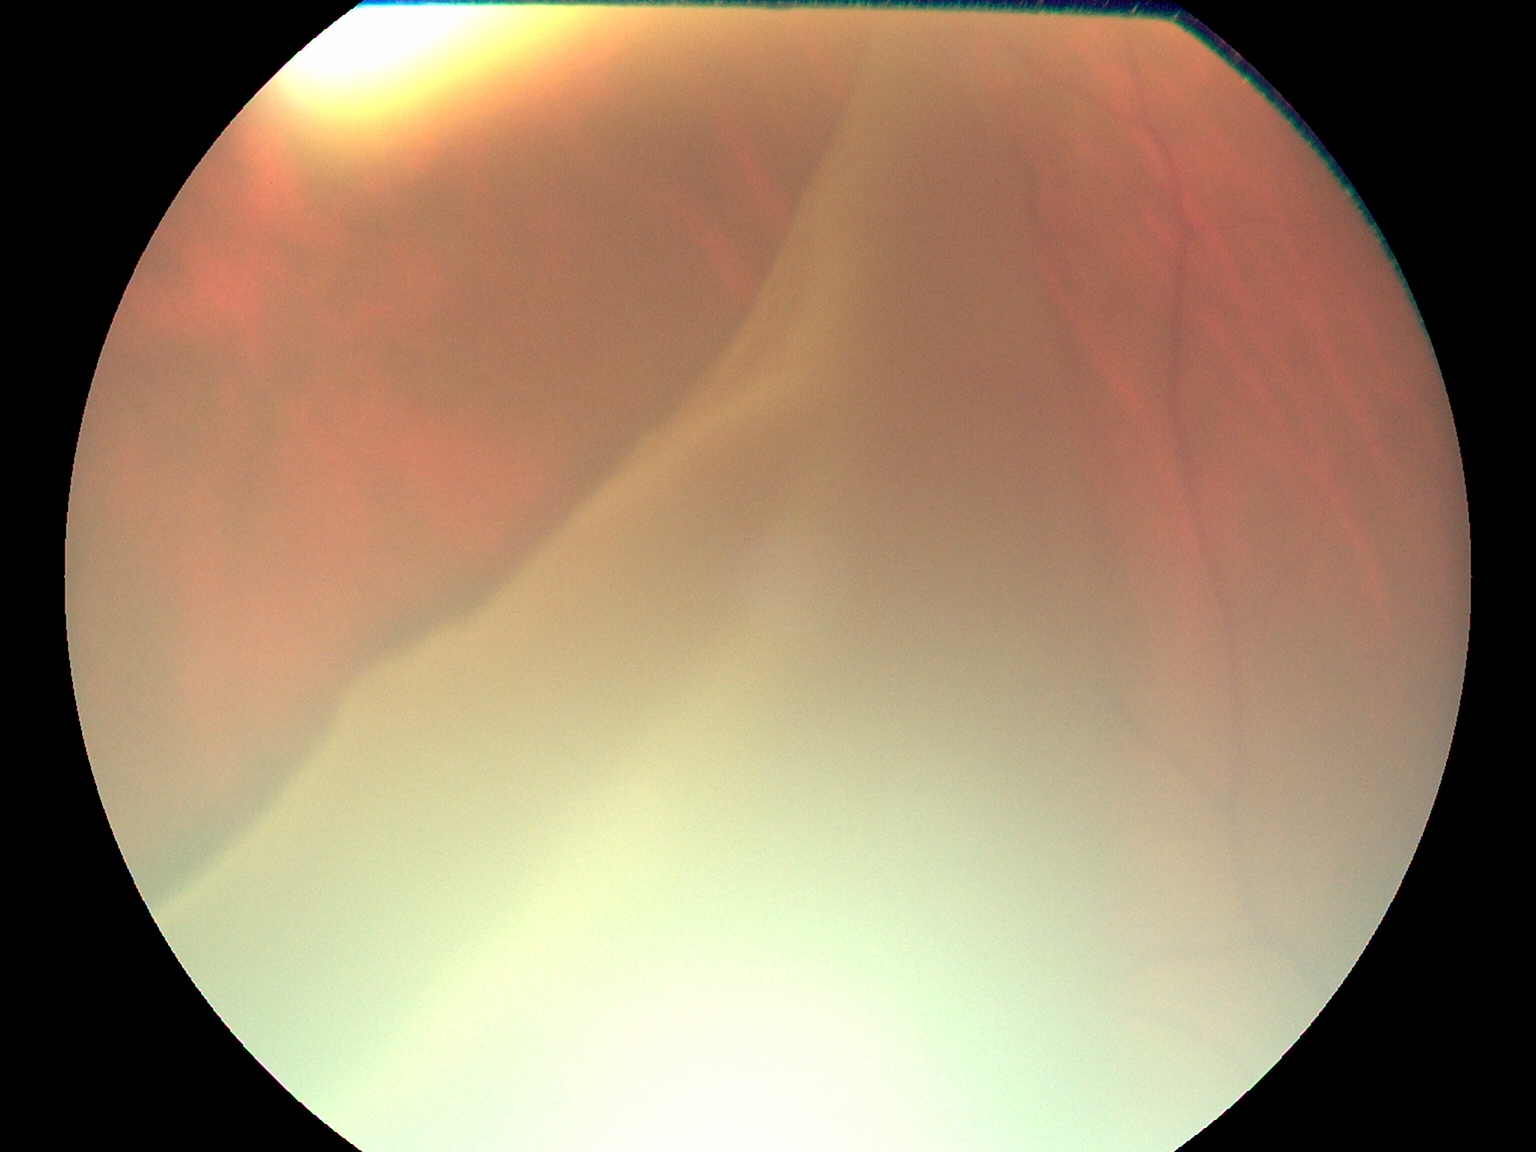

Top Retina Specialist

Advanced Retina Treatment